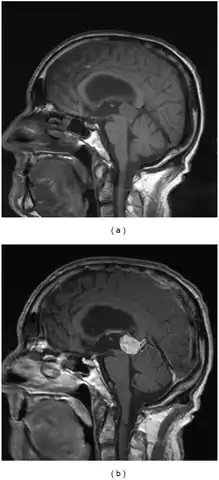

a,b)Parinaud's syndrome- sagittal and postcontrast sagittal images pineocytoma compressing the midbrain tectum

a,b)Parinaud's syndrome- sagittal and postcontrast sagittal images pineocytoma compressing the midbrain tectum Cross section of midbrain. The area affected in Parinaud's syndrome is indicated by the striped region.

Diagnosis can be made via combination of physical exam, particularly deficits of the relevant cranial nerves. Confirmation can be made via imaging, such as CT scan or MRI.